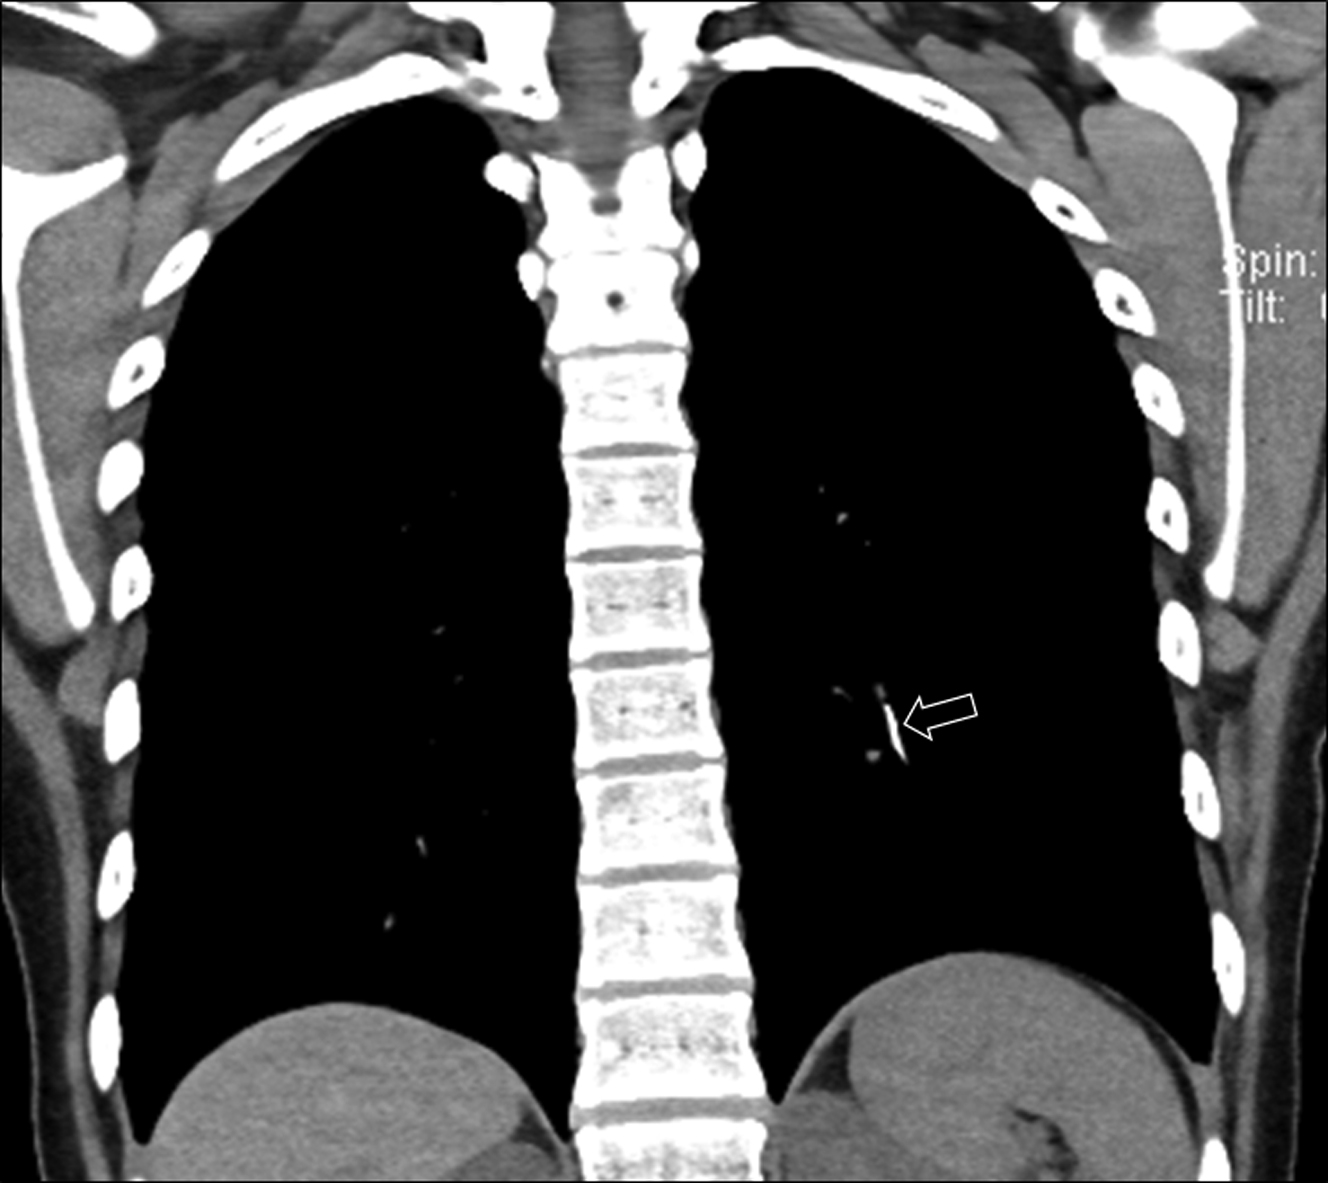

From www.ccjm.org

Air embolism after peripheral IV contrast injection Cleveland Clinic Pediatric Air Embolism as a result of its high chance of mortality and morbidity, physicians should be well equipped to prevent, identify, and. air embolism.prognosis of air embolism are reviewed here. Embolization of thrombi, amniotic fluid, fat, or tumor is discussed. we present a case of gas embolism occurring in the immediate. This article provides a systematic review of the. Pediatric Air Embolism.